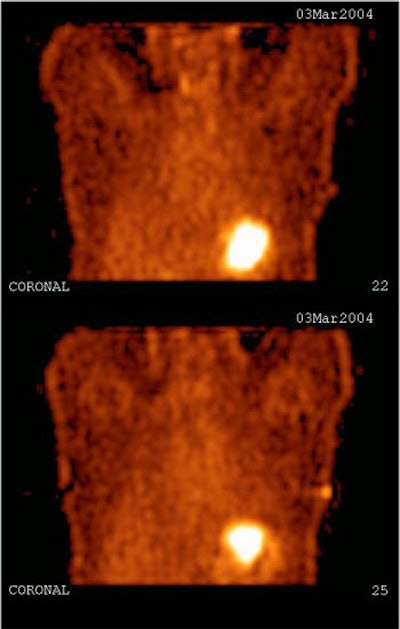

![]() |

| Study of the same patient with 25.4 mCi of Tc-99m-labeled EC-DG shows no focal areas of abnormality. Activity is noted in the stomach as well as the thyroid, indicating the presence of free pertechnetate. Images courtesy of Cell>Point. |